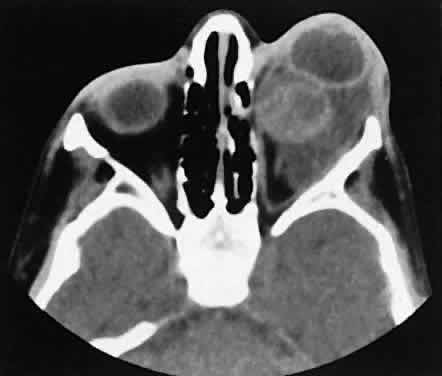

Fig. 6. Nonspecific inflammatory dacryoadenitis. An isodense enlargement of the lacrimal gland is noted on axial (A) and coronal (B) views. Note the similarity to Figure 18.

Fig. 18. Axial (A) and coronal (B) views of lacrimal gland lymphoma. There is homogenous enhancement of the enlarged lacrimal gland. Compared with Fig. 6, there is no difference.